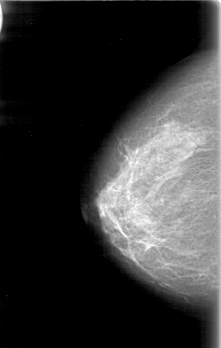

D_4054_1.RIGHT_MLO

RIGHT_CC LINES 5206 PIXELS_PER_LINE 3301 BITS_PER_PIXEL 12 RESOLUTION 43.5 NON_OVERLAY

RIGHT_MLO LINES 5116 PIXELS_PER_LINE 3181 BITS_PER_PIXEL 12 RESOLUTION 43.5 NON_OVERLAY